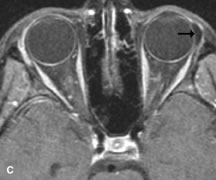

PATIENT PREPARATION Before MRI is performed, patients must be screened and prepared to avoid the potential hazards associated with the strong magnetic field. Patients who have ferrous aneurysm clips or cardiac pacemakers, who depend on life-support equipment, or who retain a possible metallic intraocular foreign body are not candidates for this imaging modality. MRI cannot be performed on obese patients who cannot fit into the bore of the magnet. Patients who are claustrophobic may not tolerate a prolonged period of study within the confines of the magnet, whereas others might do well if given a mild sedative. All worn metallic objects (e.g., necklaces, watches) should be taken off, credit cards set aside, and eye makeup removed before entering the room containing the magnet.5,20,34,35,36 NORMAL ORBITAL ANATOMY T1-weighted images provide the best anatomic details of the orbit because they display superior contrast resolution between normal structures (see Fig. 8). The vitreous has a long T1, resulting in an intermediate signal similar to brain, whereas the crystalline lens and sclera appear dark because of a longer T1 and short T2. The extraocular muscles, like all skeletal muscles, demonstrate a moderately long T1 and short T2 and highly contrast with the intense signal of the surrounding orbital fat (adipose tissue has an extremely short T1). The lacrimal glands appear as mottled areas of reduced intensity of the signal from the orbital fat in the lacrimal fossa. The optic nerves are seen with the same signal intensity as brain white matter and are hypointense relative to the orbital fat because their Tl is longer than the Tl of fat but shorter than the Tl of water. Cortical bone is not well delineated because it contains little free water, yielding minimal signal in MRI, and thus appears dark on all pulse sequences. This feature explains why MR images of the orbital apex and intracanalicular portion of the optic nerves are superior to comparable CT scans. Partial volume averaging of the bones in these regions obscures soft tissue details on CT images, whereas MRI reveals the signals only from the soft tissue structures with no cortical bone input. Bone marrow, on the other hand, is seen as a relatively intense signal because of its high fat content (see Fig. 8).37,38 T2-weighted pulse sequences are not ideal for imaging normal anatomy; however, they are particularly useful in revealing pathologic conditions (see Fig. 9). T2-weighted studies are most easily recognized by a bright vitreous signal. ORBITAL DISEASES Vascular Lesions Cavernous hemangiomas appear as well-circumscribed, smooth, usually intraconal masses that are isointense to muscle on T1-weighted images and hyperintense on T2-weighted images (Fig. 12). Patchy early enhancement is typically followed by diffuse, more homogeneous enhancement.39 The internal architecture of the mass, including septation and internal vasculature, may often be appreciated with high-quality orbital imaging.40 Lymphangiomas consist of ectatic vascular channels within a connective tissue stoma with varying degrees of lymphoid cellularity. On MRI, these tumors are typically poorly circumscribed, multicompartmental, and heterogeneous, often showing cystic dilations with fluid levels (Fig. 13). The signal characteristics within lymphangiomas vary considerably, reflecting cystic and solid components and the varying paramagnetic characteristics of blood at different stages of degradation.40–42 Acute hemorrhage appears hypointense on both T1- and T2-weighted formats. Methemoglobin present in subacute hemorrhage (3 to 14 days) leads to hyperintense signal on both T1- and T2-weighted images.41 A small percentage of lymphangiomas appear radiologically indistinct from orbital cavernous hemangiomas.43 Orbital varices are venous malformations that expand with increased systemic venous pressure, such as with Valsalva maneuvers. Because rapid acquisition of images during a Valsalva maneuver is important in imaging such a lesion, conventional or spiral CT is currently the modality of choice.44 MRI is an excellent modality for demonstrating enlargement of the cavernous sinus and dilation of the superior ophthalmic vein in patients with high-flow carotid-cavernous fistulas (Fig. 14).37MRA may be helpful in the evaluation of the venous outflow pattern. The rapidly flowing blood in these vascular structures carries the excited protons out of the section before they can be imaged, resulting in their dark appearance.5 In low-flow dural arteriovenous malformations, MRA may help define the arterial feeding vessels.45 Neural Lesions MRI is more effective than CT in delineating the intracranial optic nerves, chiasm, and optic tracts and, for this reason, is the preferred imaging modality in the evaluation of optic nerve disorders. The spatial relationships and image contrast of the orbital tissues with intraorbital optic nerve tumors is comparable between the two imaging modalities. The normal nerve is isointense to brain and appears enlarged and kinked owing to infiltration of an optic nerve glioma on T1-weighted images. Gliomas appear hyperintense on T2-weighted images and may be heterogeneous owing to cystic areas within the tumor. Contrast enhancement is variable.46 Intraorbital and intracranial optic nerve sheath meningiomas are usually isointense to cortical gray matter on Tl-weighted images and remain isointense on proton density studies (Fig. 15). Gd-DTPA is useful in delineating the intracranial extension of optic nerve meningiomas.7,47 The hyperostosis of bone and calcification associated with meningiomas are not demonstrated as well on MRI studies as on CT scans.20,37 Gd-DTPA–enhanced MRI also appears promising in the study of the permeability of the blood–brain barrier in selected optic neuropathies.22,48 MRI may reveal an enlarged optic nerve and some degree of contrast enhancement in cases of optic neuritis.49 Muscle Disorders Extraocular muscle enlargement in patients with thyroid-associated orbitopathy is demonstrated equally well with CT and MRI studies. However, the superior tissue contrast on MR images reveals better details of the relationships of the optic nerve to the thickened muscles at the orbital apex (Fig. 16).50 In addition, MRI may be able to differentiate between muscles that are enlarged as a result of edema and active inflammation and those enlarged because of fibrosis by their T2 relaxation times.21 Quantitative MRI was not found to be accurate in predicting the success of low-dose orbital irradiation.51 However, a muscular index relating the diameters of the rectus muscles to the bony orbital dimensions was useful in predicting optic nerve compression.52 MRI is also effective in imaging orbital tumors of mesenchymal origin, such as rhabdomyosarcoma, particularly in the assessment of extension into the anterior and middle cranial fossae (Fig. 17).37 The lack of any pathognomonic radiologic features necessitates rapid orbital biopsy when rhabdomyosarcoma is suspected. Osseous Lesions In general, CT is the imaging modality of choice when details of quantity and quality of bone are needed; however, abnormalities of bones can be detected indirectly by MRI. Cortical bone appears black (signal void) on MR images because of its low proton density and free-water content. The absence or discontinuity of the signal void of the orbital walls may represent bony destruction or fracture. Hyperostosis associated with prostate metastases or meningioma is visualized as areas of black smudging.50,53 Diseases in which the bone is replaced by pathologic tissues with a high free-water content, such as fibrous dysplasia, are well demonstrated on MRI. An intermediate signal intensity on T1-weighted images and hypointense signal on T2-weighted images is representative of fibrous dysplasia. Enhancement on post–Gd-DTPA MR scans is seen and is more evident in areas that are less mineralized.54 Cystic Lesions Dermoid cysts appear as rounded, well-defined lesions typically contiguous with an orbital bony suture. The high-intensity signal on T1-weighted images is attributed to the sebaceous-produced lipid contents (Fig. 18).31,50 Mucoceles may demonstrate a hypointense or hyperintense signal on MR images, depending on the concentration of proteinaceous or inflammatory fluid components. The integrity of the bony walls of the expanded sinus cavities cannot be assessed on MR as well as by CT.37,50,55,56 A high-signal intensity on Tl- and T2-weighted images is characteristic of orbital chronic hematic cysts because of the blood-breakdown products within the cysts.57 Trauma Although soft tissue relationships are usually better demonstrated on MRI, the evaluation of craniofacial bony trauma is preferable with CT. For example, prolapse of orbital fat through a fracture site and hemorrhage of adjacent tissues are demonstrated in an MR image, but the actual fractured bone is not imaged. Three-dimensional MRI of the orbit in subacute trauma has been described,58 although its precise role is not currently established. MRI has been suggested to be superior to CT in detecting intraorbital wooden foreign bodies.59,60 In a series of penetrating orbital injuries with organic foreign bodies, however, MRI was able to identify the foreign body in only four of seven cases.61 With an in vitro model for wood foreign body, McGuckin and colleagues concluded that CT was the imaging modality of choice.62 A careful history and, in selected cases, plain films to rule out a metallic foreign body are crucial before MRI is considered in patients with periocular trauma. MRI is particularly helpful in the detection and characterization of subperiosteal hematomas of the orbit (Fig. 19). They are most commonly seen in the subperiosteal space of the superior orbit as well-defined masses following a traumatic injury. The signal intensity varies depending on the acute, subacute, or chronic nature of the hematoma, based on the stage of blood degradation. Fresh hemorrhages are hypointense on T1-weighted images and hyperintense on T2 images. Hematomas that are 1 to 7 days old are hypointense on both T1- and T2-weighted images. T1-weighted images of hematomas more than a week old are hyperintense due to the oxidation of deoxyhemoglobin to methemoglobin, whereas the T2 images remain hypointense.63 Metastatic Tumors Breast carcinoma metastatic to the orbit has been demonstrated to be hypointense to the surrounding orbital fat on T1-weighted studies and hyperintense on T2-weighted images and has an affinity to the extraocular muscles (Fig. 20).50,64 The MRI characteristics of prostate carcinoma metastatic to the orbit have been described as involving the greater and lesser wing of the sphenoid, orbital roof, and optic canal. Diffuse bone hypertrophy with isointense or slightly hyperintense tissue on T1-weighted images represents the osteoblastic carcinomatous bone infiltration. Contrast enhancement is variable on T1-weighted and fat-suppressed images.65 Most other metastatic tumors also have a lower intensity signal on T1-weighted images and appear to displace or infiltrate normal orbital structures; however, their signal characteristics are variable on T2-weighted MR images.66 Many metastatic tumors demonstrate bright contrast enhancement with Gd-DTPA. Infectious Disorders MRI findings of preseptal and orbital cellulitis typically include increased signal intensities on T2-weighted images of the eyelids and orbital fat, respectively, due to the increased water content of the tissues. Since most cases of bacterial orbital cellulitis are associated with paranasal sinusitis, hyperintense signals of the affected sinuses may also be found on T2-weighted images as well as enhancement of polyps and granulation tissue on postgadolinium T1-weighted MR images. Subperiosteal abscess formation may occur due to contiguous spread of infection from the paranasal sinuses and appear on MRI as an area of intermediate signal on T1-weighted and proton-weighted MR images. The abscess may appear slightly hyperintense compared with muscle on T2-weighted scans with the necrotic contents having the greatest intensity.67 MRI and MRV are more sensitive than CT in revealing cavernous sinus thrombosis. Engorgement of the cavernous sinus, extraocular muscles, and ophthalmic veins is seen with hyperintensity of the thrombosed sinuses evident on all pulse sequences. The enlarged, thrombosed superior ophthalmic vein appears less hypointense than the normal contralateral ophthalmic vein, and hyperintensity within the lumen of the vessel may be seen on T1- and T2-weighted MR images.68 Inflammatory and Lymphoproliferative Lesions Inflammatory conditions of the orbit, both idiopathic (inflammatory pseudotumor) and those of known causes, have been found to be hypointense to fat and isointense to muscle on Tl-weighted studies and isointense or slightly hyperintense to fat on T2-weighted images (Fig. 21).50,64,69 The more fibrous or sclerosing varieties have less signal intensity on T2-weighted images. Marked enhancement is seen in pseudotumor infiltrates after gadolinium administration.70 The same signal characteristics are demonstrated in patients with Tolosa-Hunt syndrome, with mass lesions seen in the cavernous sinuses and orbital apices.71 Lymphomas have MRI characteristics similar to those of inflammatory lesions in that they are hypointense to fat and isointense to muscle on T1-weighted images (Fig. 22). They may appear hyperintense to fat on T2-weighted images, perhaps owing to less fibrosis than that seen in orbital inflammatory pseudotumor, although this is not a consistent finding.31,50,66 Lymphoid tumors typically enhance moderately after contrast injection. Unfortunately, studies have shown that tumor density and homogeneity are similar between inflammatory and malignant orbital infiltrates, and MRI cannot differentiate these lesions.72,73 Lacrimal Gland Tumors Lacrimal gland lesions present special problems in diagnosis and management. Pleomorphic adenoma (benign mixed tumor) should not be biopsied, but rather excised in toto. On the other hand, for lymphoma and inflammatory infiltrates, incisional biopsy is more appropriate than complete excision of the lacrimal gland. Thus, preoperative clinical and radiologic evaluation are especially crucial in planning appropriate surgical management. Pleomorphic adenomas demonstrate long T1 and T2 signal characteristics. They may show heterogeneity on T2-weighted images74 and moderate to marked enhancement with contrast.75 Signal characteristics of adenoid cystic carcinoma include hypointensity to fat on T1-weighted images, hyperintensity to fat with increased T2 weighting, and isointensity to fat on proton density-weighted studies (Fig. 23).31,75 Secondary bony alterations of the lacrimal fossa associated with lacrimal gland tumors, such as remodeling (benign mixed tumor) or destruction (adenoid cystic carcinoma), are seen indirectly on MR images; however, bone windows on CT scans provide better delineation of these changes. In contrast to the round or globular appearance of benign or malignant epithelial tumors of the lacrimal gland, lymphoproliferative tumors usually appear to be molding or draping onto the globe and the surrounding bony orbit. LACRIMAL DRAINAGE SYSTEM DISORDERS MRI with surface coils provides excellent spatial resolution and tissue-specific signal intensities of the lacrimal drainage system. These parameters have been found useful to more accurately demonstrate the extent of lesions in the lacrimal sac and differentiate long-standing mucoceles from solid tumors than CT.76 Physiologic studies in patients with tearing disorders now include MR dacryocystography, in which Gd-DTPA is either placed topically in the conjunctival fornix or injected by cannulation into the lacrimal sac. They provide a detailed morphologic and functional analysis of the lacrimal excretory system; however, they are no more sensitive than digital-subtraction dacryocystography or CT dacryocystography.77–79 INTRAOCULAR TUMORS On MRI, uveal melanomas have a typical appearance that helps to differentiate them from other primary and secondary intraocular tumors as well as choroidal detachments. Pigmented melanomas are hyperintense on Tl-weighted images, hypointense on T2-weighted studies, and hyperintense on proton density–weighted examinations (Fig. 24).30,31,50,80–82 These signal characteristics have been attributed to the paramagnetic properties of melanin because of stable free radicals that shorten the T1 and T2 relaxation times. Moderate enhancement is seen on postgadolinium T2-weighted images. Gadolinium-enhanced T1-weighted images are particularly sensitive in detecting choroidal melanomas.83 MRI may be less sensitive in detecting extrascleral extension of tumor than echography performed by an experienced ultrasonographer.84 Tumors metastatic to the choroid are hyperintense on T1- and T2-weighted images.24 The signal characteristics, however, may be similar to those seen with choroidal melanoma. Choroidal hemangiomas, on the other hand, have an intermediate signal on T1-weighted sequences and become hyperintense on T2-weighted images50 as well as proton density–weighted images.81 Retinoblastomas display moderate signal intensity on T1-weighted studies and a low signal on T2-weighted images.31,80,85 Calcification can be easily detected by CT and ocular ultrasonography but is not imaged by MRI.25,50 The presence of optic nerve involvement is best evaluated by MRI. ACQUIRED ANOPHTHALMIA When an eye is removed owing to tumor or trauma, an implant is typically placed in the intraconal space. MRI may be useful in defining the size, shape, and position of such orbital implants.86 Porous hydroxyapatite or polyethylene implants are preferred by many surgeons performing enucleation or evisceration. A porous implant offers the possibility of supporting a motility coupling peg to increase the movement of the overlying prosthesis. MRI with contrast is used by some surgeons to evaluate the degree of fibrovascular ingrowth in hydroxyapatite87 and porous polyethylene88 implants prior to motility peg placement. |